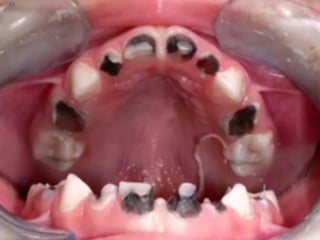

Caries de

Niñez

¿y cuando Temprana

es muy    Severa

extensa?

Para clasificarla

como  severa

hay que cumplir

ciertos criterios

Cantidad total de

superficies afectadas es

≥de 4 a los 3 años, 5 a los 4

y 6 a los 5

De esta forma se enfatiza la

seriedad de la condición